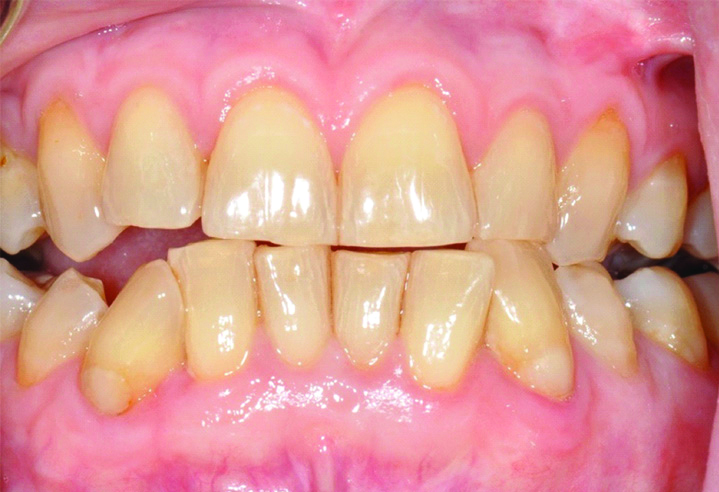

During the follow-up period, which lasted for 18 years, no adverse significant changes were noted over time. Instead, the root coverage and keratinised tissue increased over time [Table/Fig-7,8,9,10,11 and 12].

Eighteen -year follow-up images of teeth #33 and #43.